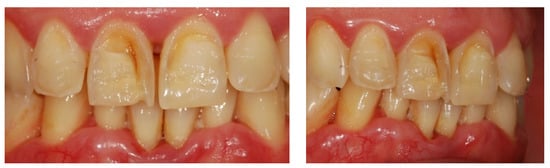

| Panic et al. (2019) [62] | Study in vitro | Ascertain how carbonated beverages affected enamel and dentin at various times. | SEM was used to assess and take pictures of 20 samples after: -60 min, -24 h, and -7 days of exposure to the drinks. ANOVA was used to examine the data. | The pH values of the drinks were below the critical pH of the enamel: after as little as 60 min of exposure there were signs of erosion. |